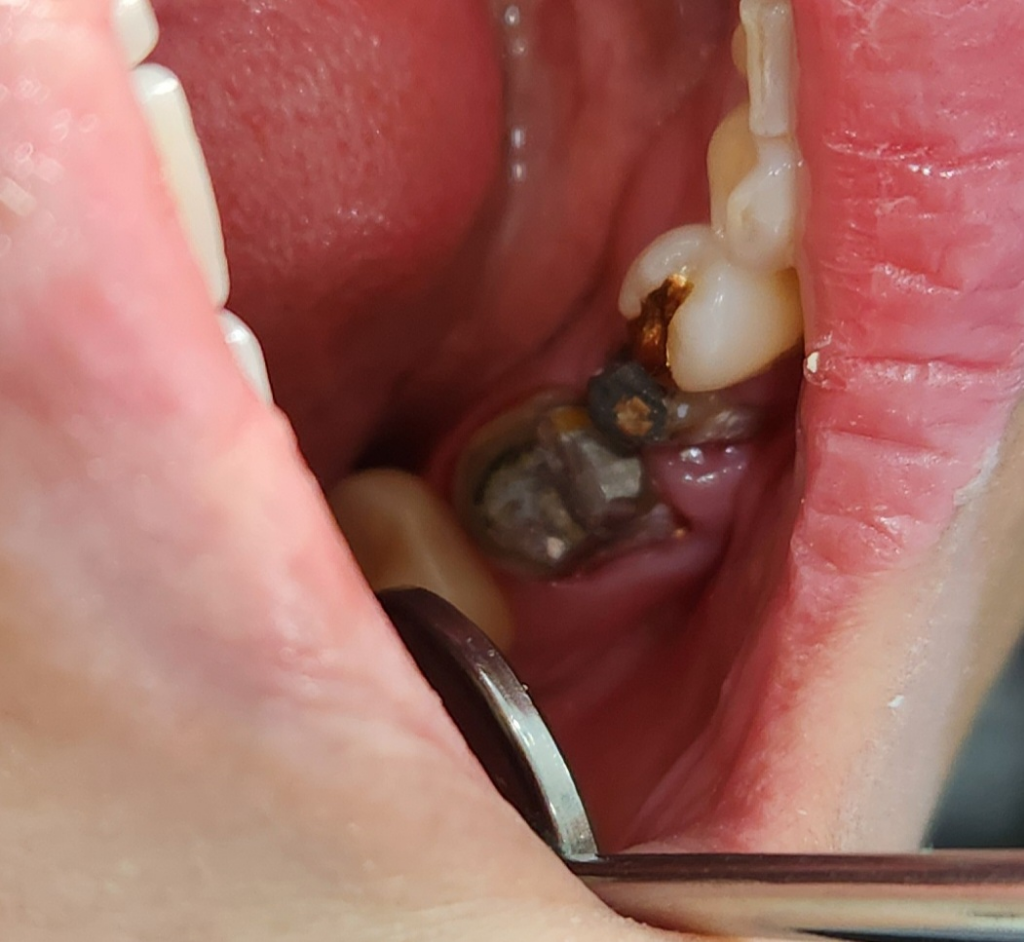

오래된 크라운을 제거하고 다시 치료중인데요

치료가 잘 된건지 불안하네요..충치를 완전히 제거하지않아도 된다는둥 이상한 소리를 들어서 더 그런것 같아요(치기공사분이 그렇게 말씀하심) 긁어봤을때 긁어지는 부분만 충치가 진행중이라 제거한다는 말씀을 하시던데요 이렇게 하고 다시 크라운을 씌워도 되는걸까요? 의사샘이 짧게 치료하시고 거의 치기공사분이 맡아서 하는 치과가 솔직히 믿음이 안가고 불안하고 해서요. 큰체인점 치과라 이런 시스템으로 하는것 같아요 이 상태에서 임시치아 씌우고 마무리 단계에요 어금니 두개중 작은 어금니는 충치가 깊어서 긁어냈다고 하는데 잇몸도 좀 부은것 같고 괜찮은걸까요ㅠ

• 1번 째 사진

사진상으로는 현재 어떤 상황인지 전혀 구분이 가지 않습니다. 말씀하시는 부분 중에서 긁히는 부분을 제거하고 그렇지 않은 부분은 꼭 치료하지 않아도 되는 것이 틀린 말은 아니나 현재 치아가 그러한 것에 해당하는지에 대해서는 임상 검사를 해보아야 할 것으로 보입니다. 단순히 사진만으로는 구분이 힘듭니다.

잇몸이 많이 부어 잇는거 같긴합니다. 일반적으로 저상태라면 잇몸이 가라 앉을때까지 일단 좀 기다려야될것같습니다. 그리고 충치를 제거하고 저기에 보이는 검정색은 충치가 아니라 예전에 신경치료를 하시고 기둥을 세워 놓은신거 같습니다.

아말감으로 인해서 색상이 변한 부위를 제거를 하지 않을수 있어요.